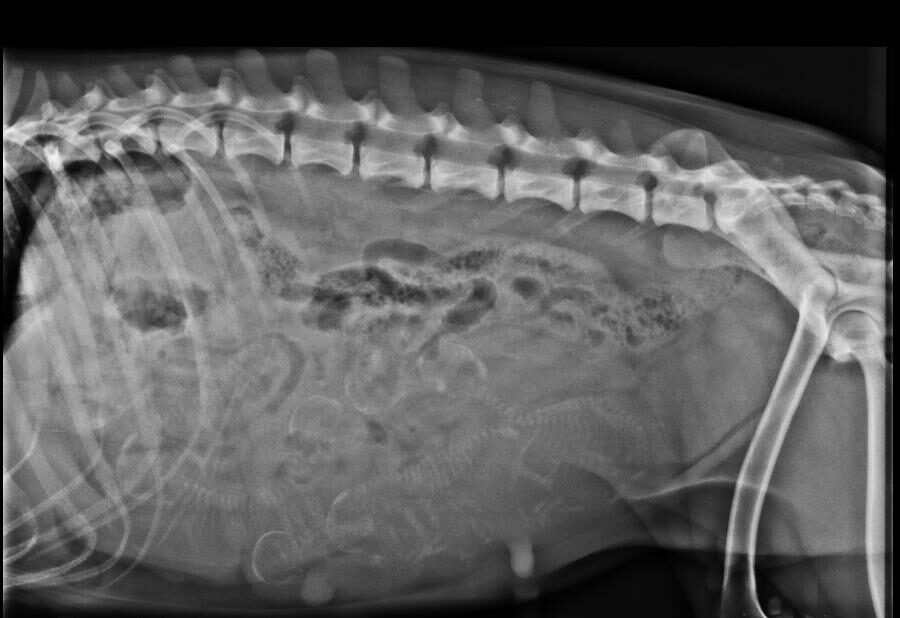

Bij een röntgenfoto wordt er met behulp van röntgenstralingen een opname gemaakt van de binnenkant van het lichaam. Bepaalde weefsels in het lichaam houden de röntgenstralen tegen, terwijl andere ze gemakkelijk doorlaten. Hierdoor is het mogelijk om verschillende structuren in het lichaam op een röntgenfoto te zien.

Röntgenfoto’s kunnen worden gebruikt om verschillende aandoeningen en problemen te helpen diagnosticeren, variërend van botbreuken tot problemen met interne organen zoals de longen, lever en nieren. Ook worden röntgenfoto’s gebruikt voor het maken van officiële HD/ED-röntgenfoto’s voor het beoordelen van de heup- en ellebooggewrichten bij bepaalde hondenrassen.